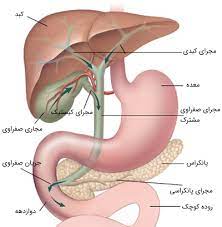

قیمت: 96٬000 تومان - دسته بندی فایل: پاورپوینتپاورپوینت کبد ، دستگاه صفراوی و لوزالمعده طرح های بافت شناسی آزار کبدی (ppt) 433 اسلاید

فروش ویژه پاورپوینت حرفه ای کبد ، دستگاه صفراوی و لوزالمعده طرح های بافت شناسی آزار کبدی / تعداد اسلاید: 433 اسلاید